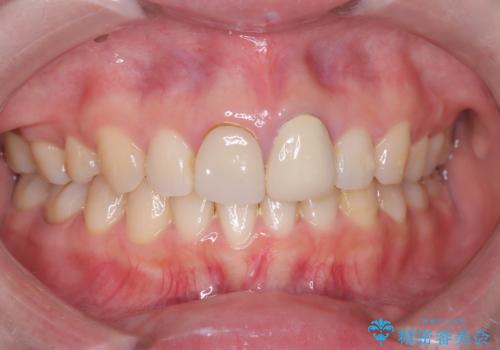

突き出た前歯を下げて理想的な横顔に。上下左右4番抜歯による審美ワイヤー矯正